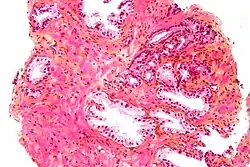

The prostate consists of glandular and connective tissue.[2] Tall column-shaped cells form the lining (the epithelium) of the glands.[2] These form one layer or may be pseudostratified.[4] The epithelium is highly variable and areas of low cuboidal or flat cells can also be present, with transitional epithelium in the outer regions of the longer ducts.[10] Basal cells surround the luminal epithelial cells in benign glands. The glands are formed as many follicles, which drain into canals and subsequently 12–20 main ducts, These in turn drain into the urethra as it passes through the prostate.[4] There are also a small amount of flat cells, which sit next to the basement membranes of glands, and act as stem cells.[2]

The connective tissue of the prostate is made up of fibrous tissue and smooth muscle.[2] The fibrous tissue separates the gland into lobules.[2] It also sits between the glands and is composed of randomly orientated smooth-muscle bundles that are continuous with the bladder.[11]

Over time, thickened secretions called corpora amylacea accumulate in the gland.[2]

Histology of normal prostate, H&E stain, with benign features: Glands are rounded to irregularly branching, with an inner layer of epithelial cells surrounded by an outer layer of basal cells. They are surrounded by ample stroma. -

Histology of prostate with gradually increasing simple atrophy from left to right, H&E stain. Crowding and angulation may mimic that of adenocarcinoma, but there is nuclear basophilia rather than atypia, and occasional basal cells can still be seen.